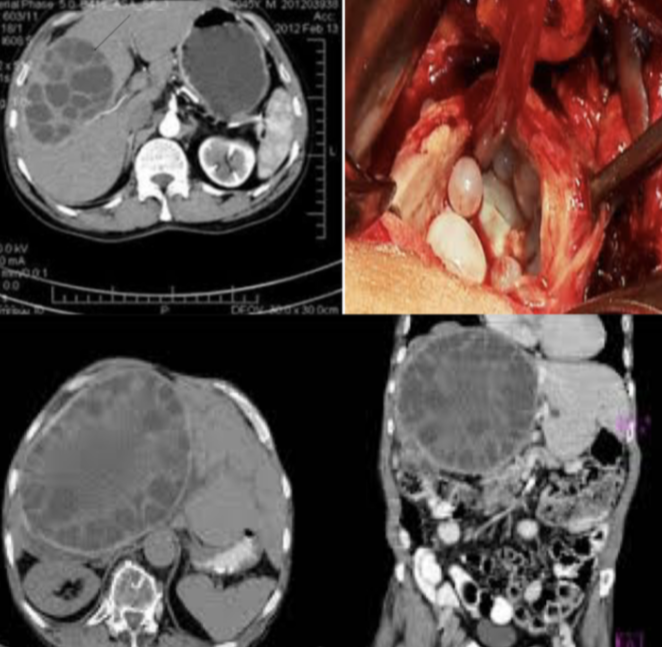

Diagnosis?

hydated cyst

Causative organism? Echinococcus granulosus

Causes?

Treatment? medical

- Asymptomatic no treatment - may be treated with albendazole or mebendazole but this may be prolonged

Surgery

- Deroofing and complete excision of the endocyst

- Complete excision of the cyst (pericystectomy)

- Selected patients with central liver cyst may be suitable for puncture – aspiration-injection-re-aspiration (PAIR)